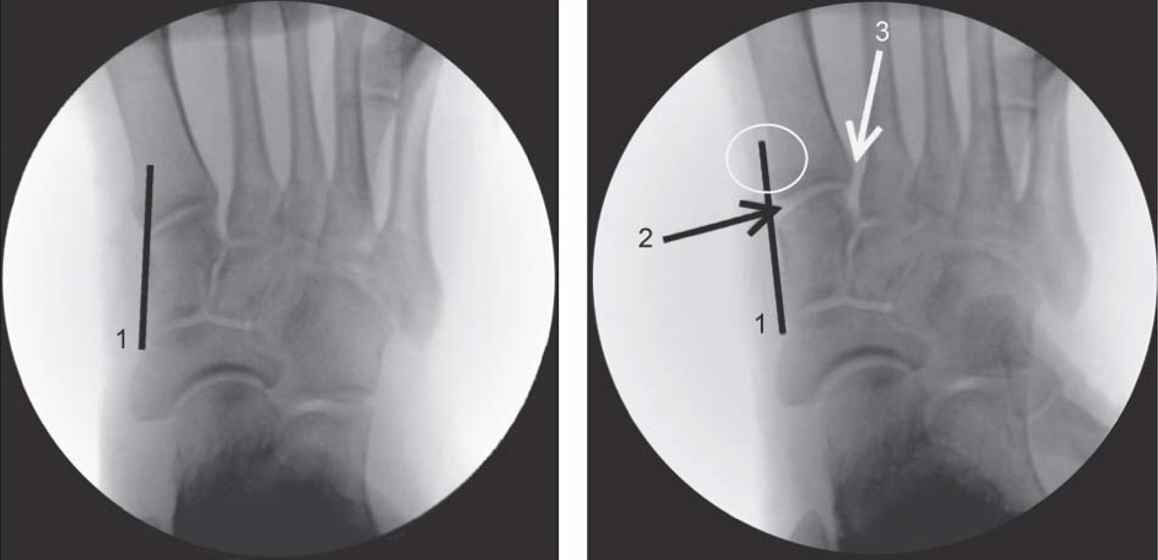

A tangent placed along the medial border of the medial cuneiform should intersect the base of the first metatarsal. In the case of medial TMT instability with forefoot abduction stress, this tangent passes medial to the base ("medial column sign" positive) (Fig. 15).

Similar to this technique, the stability of the ligamentous connections can be assessed using a dynamic radiographic stress test. Coss et al (28) demonstrated that the displacement of the medial column line was due to incompetence of the Lisfranc ligament combined with the dorsal TMT ligament. The positions of the base of the second metatarsal on the AP projection and the fourth metatarsal on the oblique projection are the main indicators of instability of the TMT complex. However, the importance of using weight-bearing radiographic studies in this context must be emphasised. Shapiro et al (29) provided evidence of the insufficient validity of unloaded images compared to analysis of loaded radiographic images in distinguishing stable and unstable TMT lesions. (Fig. 16)